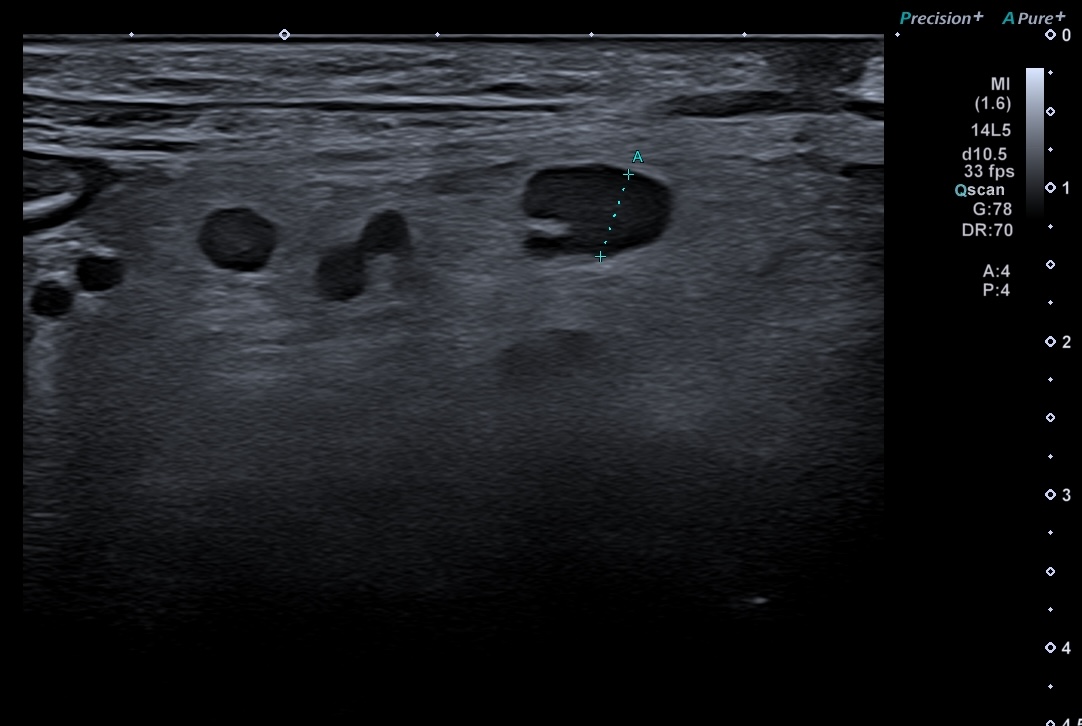

Ci-dessous ganglions de petite taille (5 mm) arrondis, hypo échogènes et situés au sein d'une inflammation de la graisse